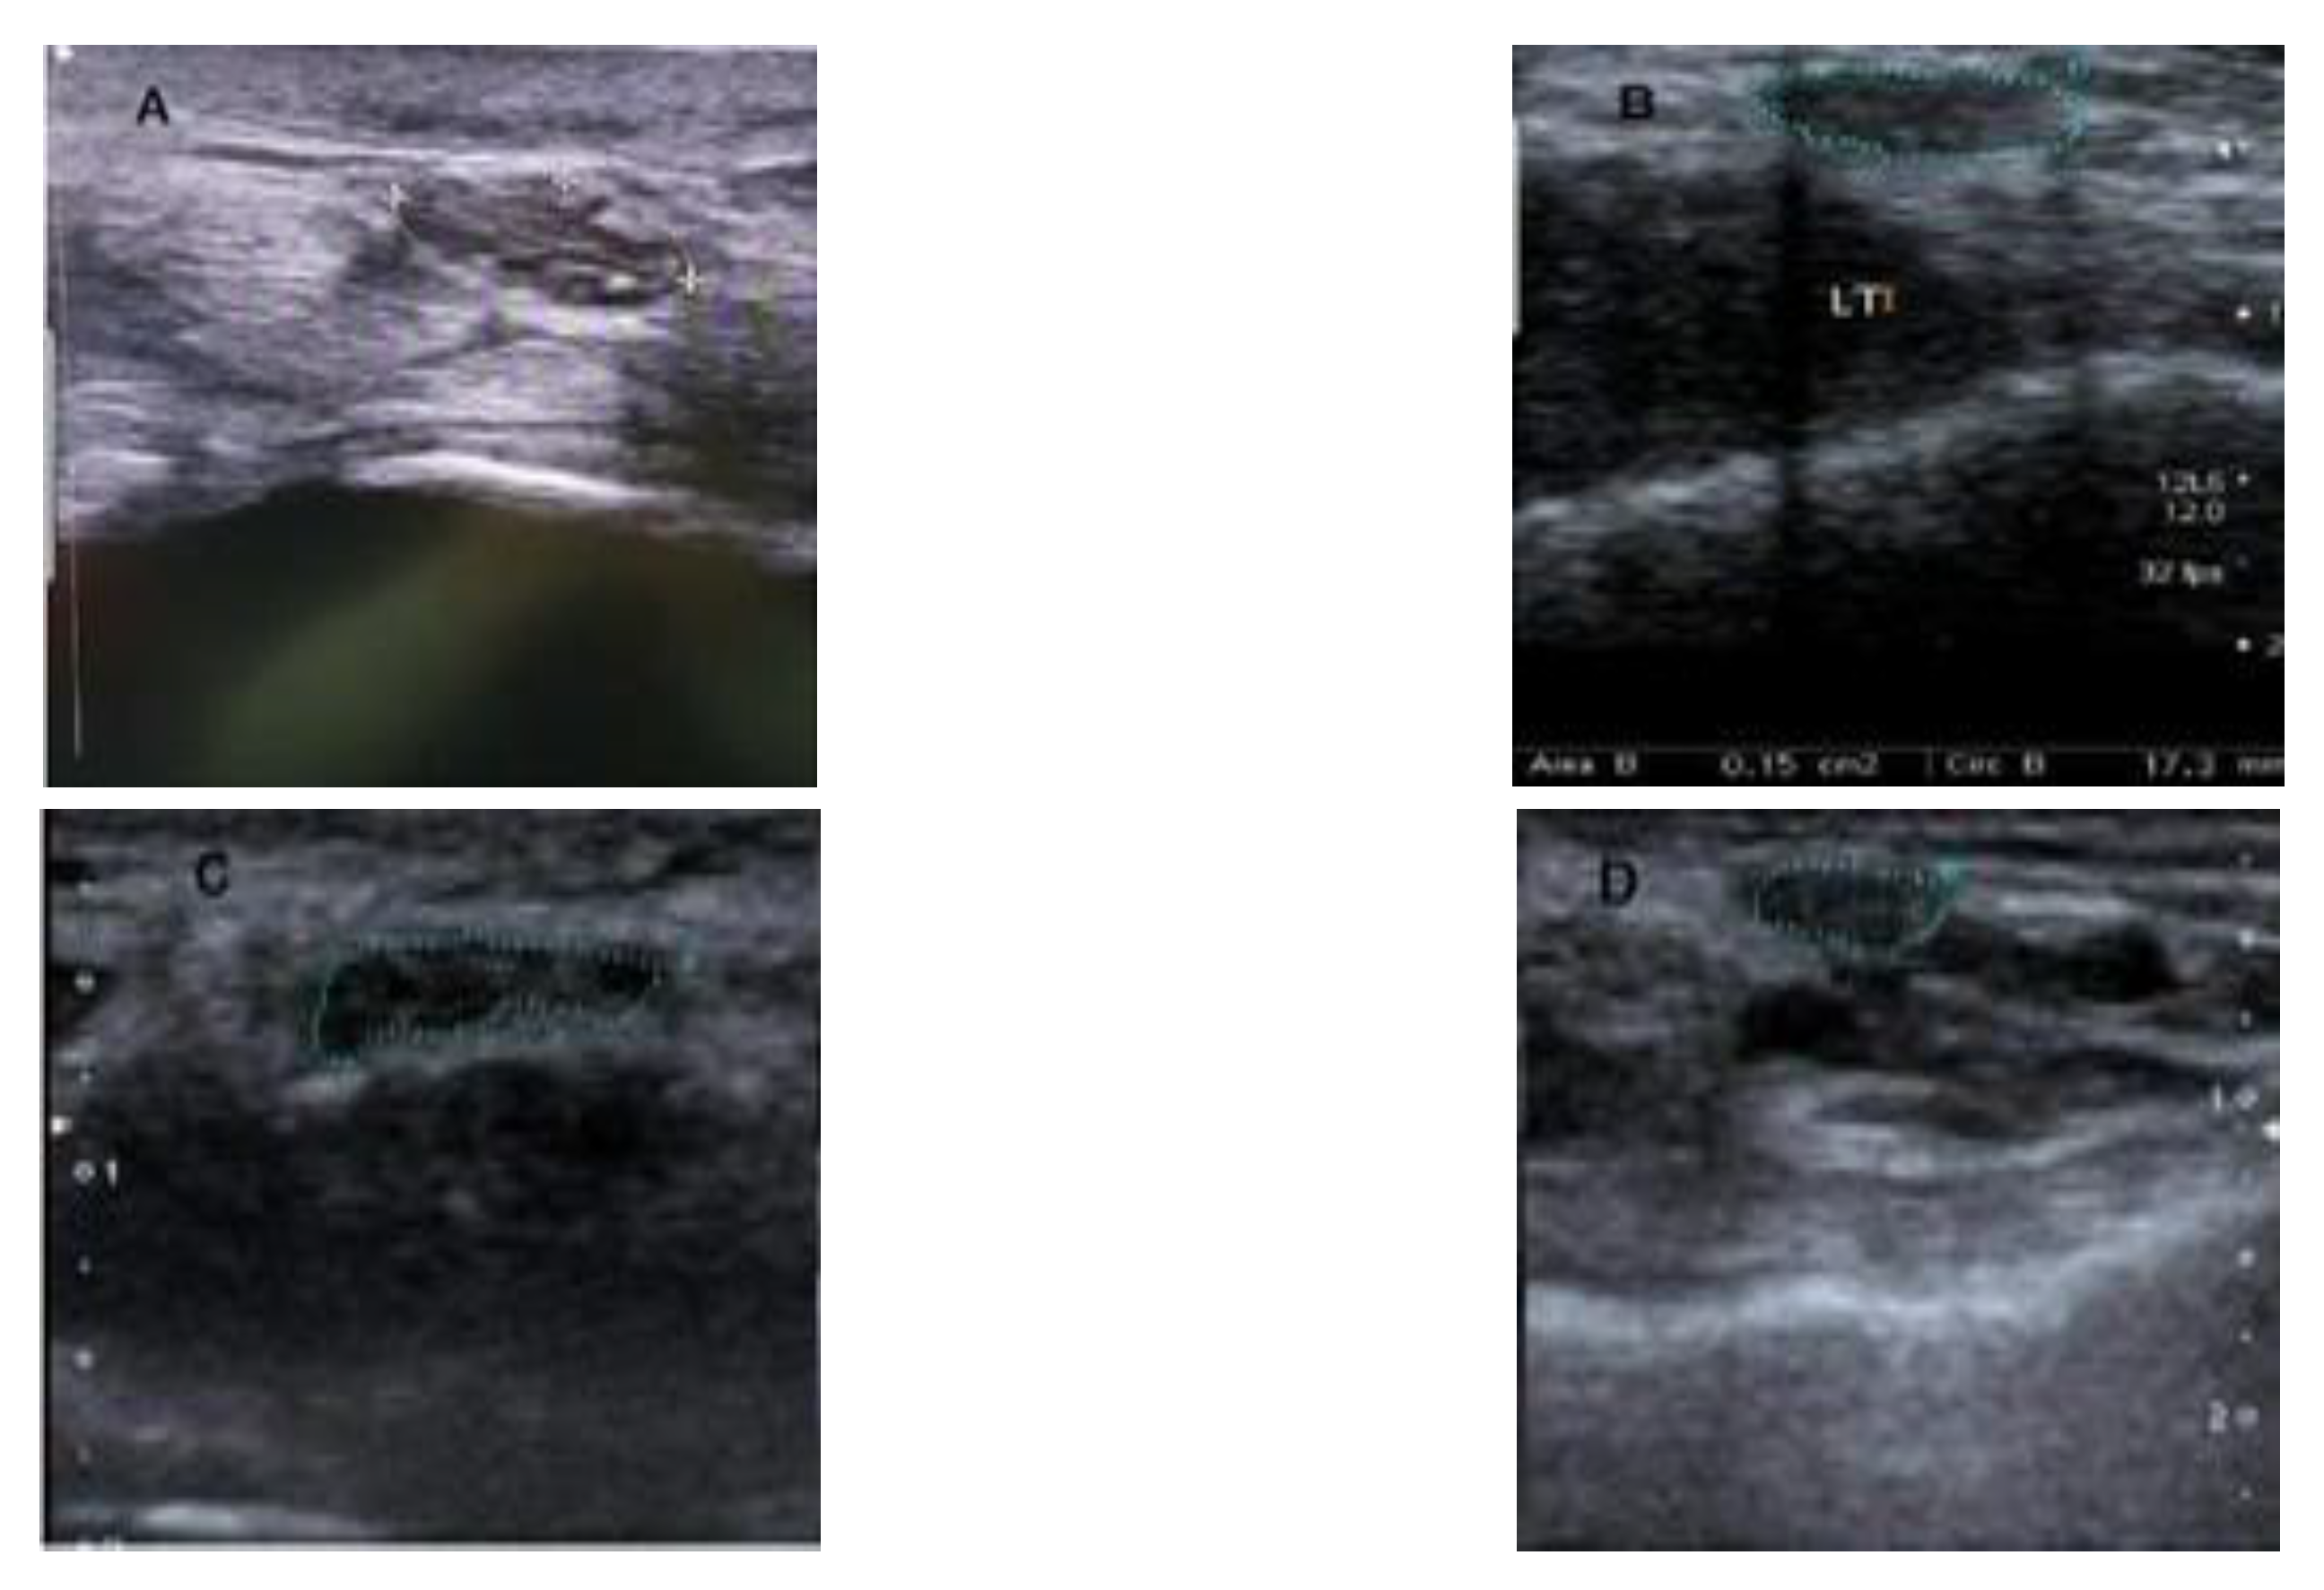

3.1.1. Dataset Collection

3.1.2. Study Cohorts